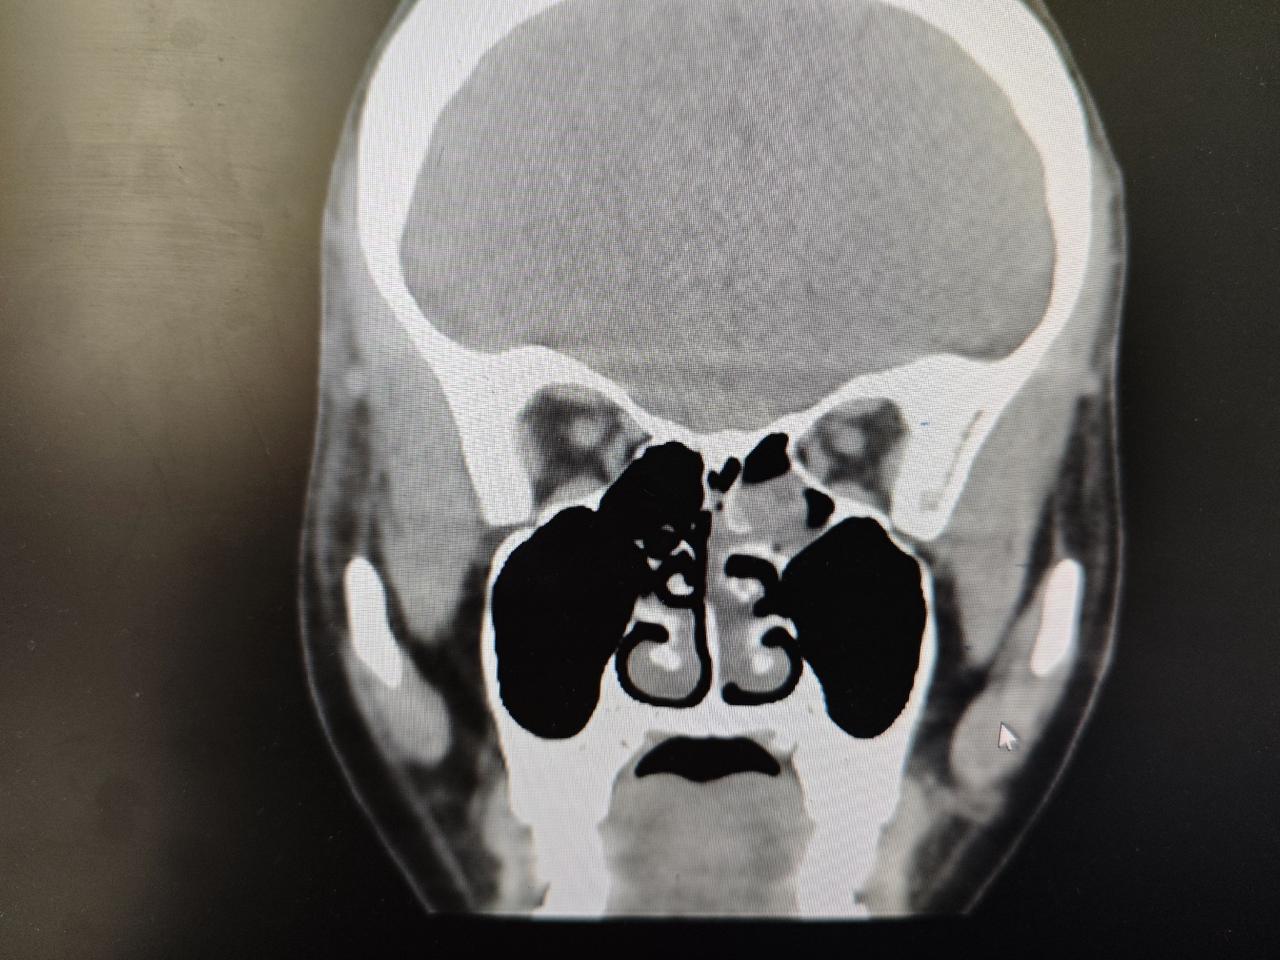

内翻性乳头状瘤,术后半年复查,预后良好

左侧鼻腔鼻窦内翻性乳头状瘤,术后三年复查,创面完全愈合,没有复发

鼻腔鼻窦内翻性乳头状瘤术后三年复查,创面完全愈合,没有复发